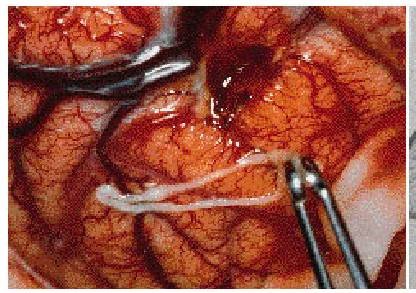

Hình 3: Sparganum được gắp ra từ vỏ não chẩm phải

(Nguồn: https://web.stanford.edu)